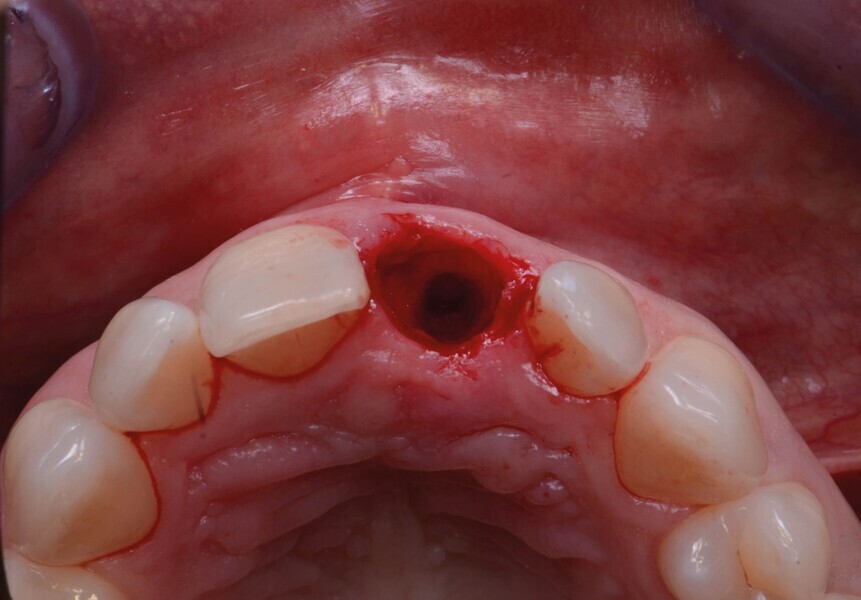

La dent 21 est extraite de la manière la moins traumatique possible à l’aide d’un périotome (Fig. 4). Elle est conservée dans du sérum physiologique afin de pouvoir l’utiliser comme restauration provisoire par la suite.

Fig. 4 : Extraction atraumatique de la dent 21.

Fig. 5a : Après l’extraction

Fig. 5b : Après l’extraction